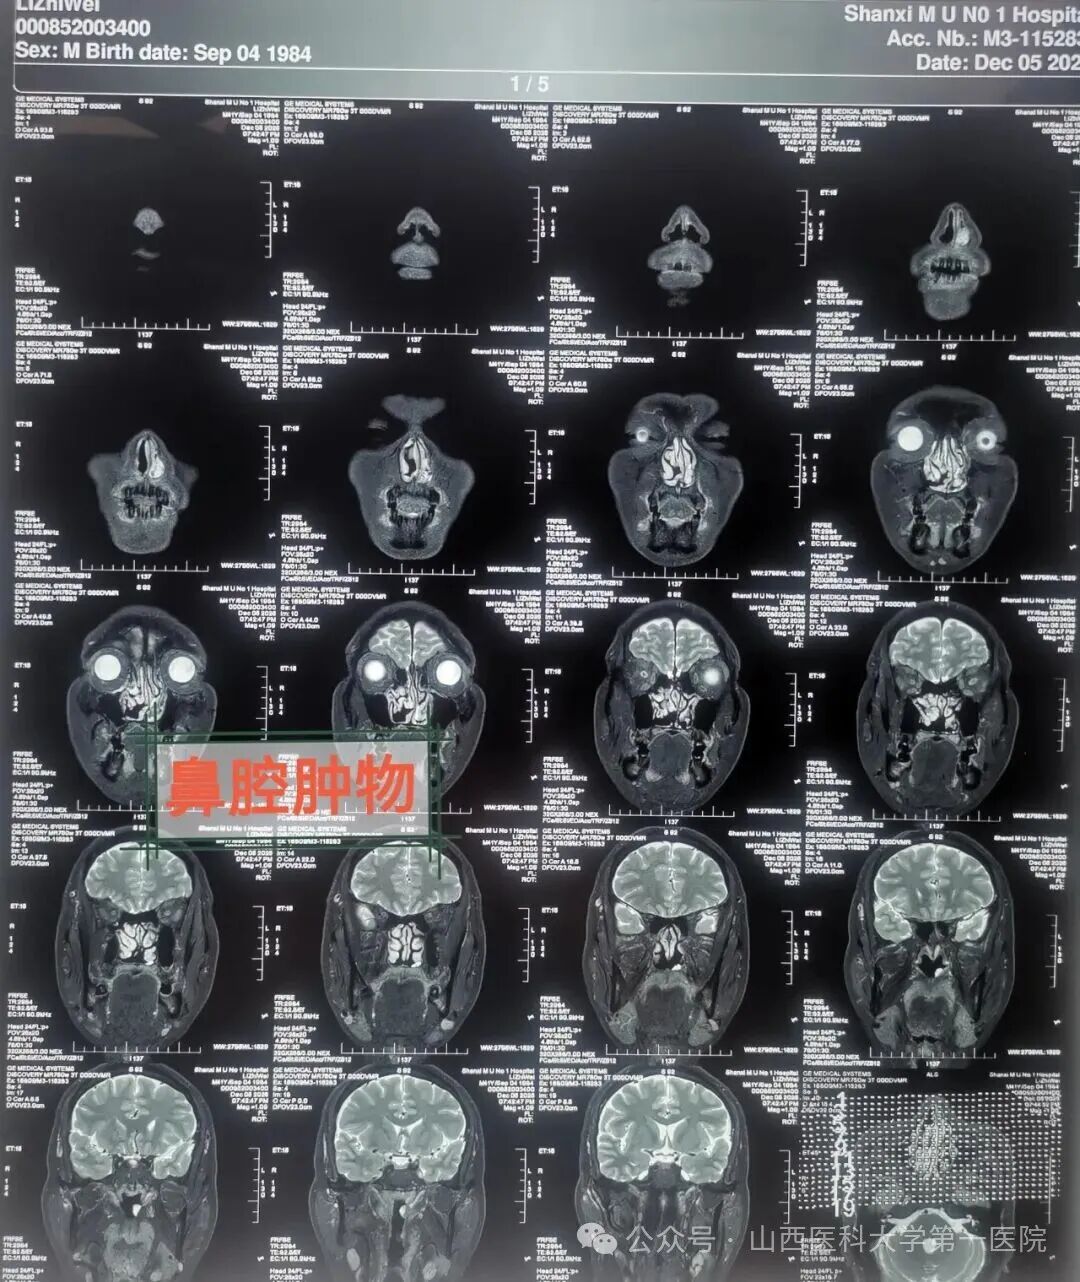

耳鼻咽喉-头颈外科,通过鼻内镜检查及医学影像学检查,初步考虑为鼻腔恶性肿瘤。办理住院手续后完善各项检查后,安排手术治疗,全科病例讨论后确定外科手术治疗方案,由柴向斌教授主刀、王洋术中配合,鼻腔肿瘤已侵犯鼻腔黏膜与鼻中隔黏膜,采用鼻内镜鼻腔进路手术,暴露术野,明确肿瘤界限,完整切除肿瘤。

柴向斌讲到,鼻腔恶性黑色素瘤来源胚胎神经嵴,起源鼻腔黏膜中树状突黑色素细胞,属弥漫的神经内分泌系统。病因不明确,可能与遗传因素、环境因素等有关联,鼻腔恶性黑色素瘤多见于鼻中隔和鼻腔外侧壁,早期症状为渐进性鼻塞、鼻出血,肿瘤多为棕黑色;晚期常充塞鼻腔,将鼻中隔推向对侧,通常侵犯邻近鼻窦、鼻咽部、眼眶和牙槽等。鼻腔恶性黑色素瘤以鼻塞、鼻出血、涕中带血丝为临床主要三大症状,内镜检查以息肉样外观伴表面灰褐色坏死为特点,通常恶性程度比较高,生存期短,并且早期诊断较困难,治疗难以彻底,易误诊、易复发、易转移,预后差,属于临床难治疾病。目前手术治疗为最佳措施,同时手术后配合免疫治疗等。

柴向斌强调,患者出现渐进性鼻塞、鼻出血等症状时,要及时就诊,尽量避免漏诊与误诊。医生会对患者进行全面体格检查,然后可能建议患者做CT、MRI、病理检查等,以明确诊断,为后续制定科学、个性化的治疗方案奠定基础。